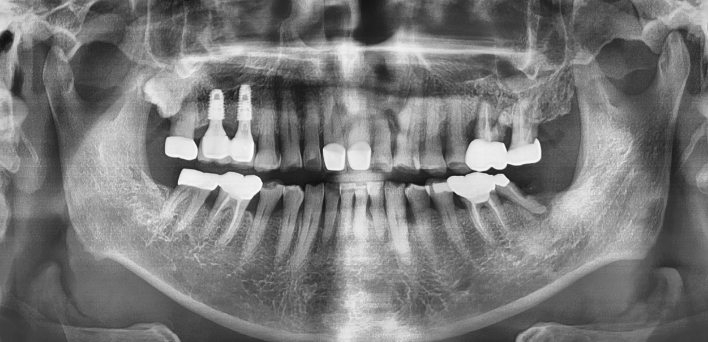

임플란트 : 손 ** 님 (50대)

치아가 있다는게, 아직도 정말 꿈만 같아요.

Before Before

2020.02.30

After After

※ 더서울치과의원은 의료법을 준수하며 위 케이스는 실제 환자의 동의를 얻은 사례로 치료 전, 후가 동일한 환경에서 촬영되었습니다.

환자 케이스에 따라 부작용이 발생할 수 있습니다. 이 부분은 의료진의 충분한 상담과 체크를 통해 예방하고 줄일 수 있습니다.

[임플란트 부작용] 수술 후 관리가 소홀할 경우 출혈, 주위염 등의 부작용이 발생할 수 있어 구강 위생을 철저히 유지하고, 정기적인 검진을 통해 상태를 점검하는 것이 중요합니다.

환자 특징

환자 특징01무치악 상태

환자 특징02수년간 무치악으로 지내심

임플란트가 불가능할것이라

생각하고 내원

위, 아래 6개씩 식립

디지털 풀아치 임플란트